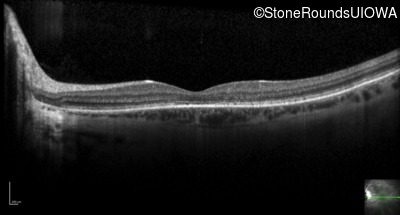

Optical Coherence Tomography - Left - 20/32

Exemplar / OCT Stack

OCT Stack